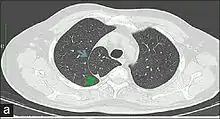

In human anatomy, an azygos lobe is a normal anatomical variation of the upper lobe of the right lung.[1] It is seen in 1% of the population. Embryologically, it arises from an anomalous lateral course of the azygos vein,[2] in a pleural septum within the apical segment of the right upper lobe or in other words an azygos lobe is formed when the right posterior cardinal vein, one of the precursors of the azygos vein, fails to migrate over the apex of the lung and penetrates it instead, carrying along two pleural layers as the azygous fissure, that invaginates into the upper portion of the right upper lobe.[1]

An azygos lobe is usually an incidental finding on chest x-ray or CT scan, and is not associated with any morbidity.[3][4] However, it can cause technical problems in thoracoscopic procedures.[5]